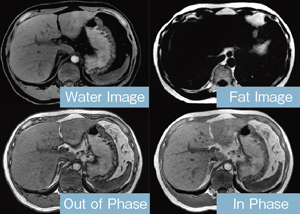

Mri t1 t2 腹部. Mriはctと違いx線を使わないため放射線被ばくになることはありません。 mri画像の色の違いとは? mriもct同様に白と黒で画像表示されます。 mriでよく使うのがt1画像とt2画像です。 t1とt2の見え方については表をご覧ください。 t1画像. 現在、当クリニックでは上腹部MRI検査として、横断像を4シーケンス<T1(in、 out Phase)T2 HeavyT2 DWI>、冠状断を1シーケンス<HeavyT2>を撮影ルーチンとしております。スライス厚は5mmを基本として35枚程度の撮影です。. Open MRIの高い性能を感じ取ることができる。 (1) 基本的シーケンス Open MRIでは、MRI検査に必要な基本シーケンスを撮像 することができる。具体的にはT1強調画像、T2強調画像、プ ロトン密度強調画像、T2*強調画像、MRAngiographyなど である。.

MixiMRI勉強会 脂肪抑制いろいろ 最近やっと勉強する気になったのですが、疑問が次から次へと出てきます。ここでは脂肪抑制についてお聞きしたいと思います。 脂肪抑制にもいろいろありますよね。 T2、PD、T1など。また、SE系、GRE系の違いもありま. ・骨盤部ではmriを,腹部ではctを第一選択にする. ・t1強調画像ではt1が長いほど磁化の回復が遅れるため信号が低く(黒く),t2強調画像ではt2 が長いほど磁化の減衰が遅れるため信号が高く(白く)描出される.t1とt2の組み合わせで組 t1強調画像はctの画像と似ており、脳の解剖学的な構造が見やすいという特徴があります。. 造影剤投与によりT1緩和時間が大きく短縮されますので基本的に脂肪抑制T1強調画像をベースに撮影が行われます。 ③実際の症例を提示します。 1) Stage I 腎細胞癌のdynamic MRI画像です。 左腎臓上極に1cm大の遷延性濃染する腫瘍を認めます。.

MRIは、磁気共鳴画像(Magnetic Resonance Imaging)の略称で、 強い磁石 と 電波 を使って体の断層像を撮る検査です。 MRIの原理は、まず強い磁気の中で、患者さんに外から電波を体に加えます。. ・骨盤部ではmriを,腹部ではctを第一選択にする. ・t1強調画像ではt1が長いほど磁化の回復が遅れるため信号が低く(黒く),t2強調画像ではt2 が長いほど磁化の減衰が遅れるため信号が高く(白く)描出される.t1とt2の組み合わせで組織 の成分が推定できる.. Mri造影剤は、mriにおける体内構造の可視性を向上するために使われる造影剤 。 コントラストの強調にはガドリニウムという化合物が最も一般的に使われる。 このmri造影剤は経口投与もしくは静脈投与(angio)により体組織内の核の緩和時間を短縮する。.

MRI(magnetic resonance imaging)検査では撮像 時間が長く,上腹部の検査では,呼吸による動きによ ってモーションアーチファクト(mortion artifact:運 動アーチファクト)が発生し,読影診断に影響を与え てしまうおそれがある.呼吸のような周期的な動きに. 3T MRI が臨床に導入されてから、基本的な撮像技術の重要性がますます高まっている。本講演では、3T MRIにおける躯幹部領域のトピックスである、脂肪抑制、Volume化の流れ、非造影MRAの3点について、GE社MRIの最新アプリケーションと臨床的有用性を中心に紹介する。. く,造影剤が分布した周囲組織のプロトンの緩和を促進(主としてt1短縮効 果)させることにより,t1強調画像で造影効果を発揮する(信号が増強される)。 しかしながら,造影剤濃度が高くなると,t2,t2*短縮効果により信号は逆に 減衰する(図1)2)。.

ガドリニウム:MRIで造影といえばこれ。 超磁性体酸化鉄粒子 SPIO:肝網内系をターゲットとした造影剤である。SPIOはKupffer細胞に貪食されリソソームにクラスター化される家庭でT2*緩和時間およびT2緩和. くはない3).mriでは,鉄沈着による局所の磁場 の不均一により,t1,t2及びt2*緩和時間が 短縮する特性を利用して肝内鉄沈着の評価が可 能である.特にt2及びt2*とそれらの逆数であ るr2及びr2*は鉄濃度と比例して変化するた 一口メモ 図3 肝生検組織所見. 頭部mriの見方です。 基本は 水 = 脳脊髄液 を見ます。 脳脊髄液は脳室や脳の表面にあります。 t1なら黒 t2なら白です。 話が難しいのは mriに….

〈medix vol.50〉 41 1.はじめに mri検査において基本シーケンスはt2強調画像とt1強調 画像である。かかりつけ医の医療の場において、診断能向上の. 頭部MRI の基礎 -頭部MRI で撮られる各画像について- 友愛会南部病院 仁井田 明 要旨 現在、日常的に撮影されている頭部MRI(Magnetic resonance imaging :磁気 共鳴画像法)画像にはT1 強調像(T1WI)、T2 強調像(T2WI)、プロトン密度強 調像(PDWI)あるいはFLAIR(FLuid-Attenuated Inversion Recovery)像. 3T MRIの組織コントラスト能の特徴 T1強調画像 de Bazelaireらの研究 1) によると,腹部領域における3Tと1.5Tの緩和時間の違いは,肝臓,脾臓,膵臓では,3TでT1値が著明に延長するのに対し,筋肉では緩和時間に差がなく,結果的に,3Tでは肝臓,膵臓,筋肉でのT1値の差が少なくなる。.

上腹部mriの見方 シーケンスを4つに分類しよう 画像診断 Com